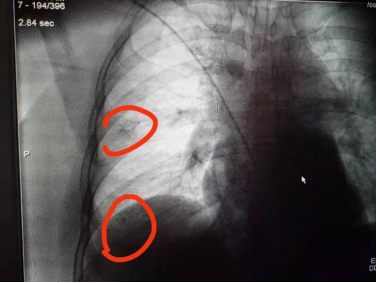

为保障万无一失,释放H-Marker前后,导航团队均利用高大上的锥形束CT进行术中实时确认。

整个手术四十分钟就结束了,CBCT确认两个H-Marker定标器位置良好。

打开胸腔后,肺结节定位清晰可见